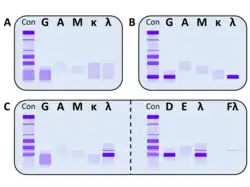

Entsprechend dem gebildeten Antikörper werden folgende Typen unterschieden:[33][34][35]

| Monoklonales Tumorprodukt | Häufigkeit | IgG | IgA | IgM | IgD | IgE | Kappa | Lambda | ||

|---|---|---|---|---|---|---|---|---|---|---|

| Ausschließlich intaktes Immunglobulin | 5–10 % | ca. 55 %* | ca. 20 %* | ca. 0,5 %* | ca. 2 %* | extrem selten | ||||

| Freie Leichtkette mit oder ohne intaktem Immunglobulin | 90–95 % | Freie Leichtkette mit intaktem Immunglobulin | 70–75 % | 57 %* | 34 %* | |||||

| Ausschließlich freie Leichtkette | 15–20 % | |||||||||

| Nicht-sekretorisch | 1–2 % | |||||||||

| *bezogen auf die Gesamtheit der Myelom-Patienten | ||||||||||

Hervorzuheben ist, dass bei einem Myelom, bei dem ein intaktes Immunglobulin gebildet wird, z. B. bei einem IgG-Myelom, in ca. 90–95 % der Fälle auch eine freie Leichtkette in erhöhter Menge vorliegt (z. B. eine freie Leichtkette vom Typ κ bei einem IgGκ-Myelom). Bei nur 5–10 % der Fälle findet sich ausschließlich ein intaktes Immunglobulin und in wenigen Fällen scheiden die Plasmazellen kein monoklonales Immunglobulin bzw. keine freie Leichtketten aus.[33] In diesen Fällen spricht man von einem sogenannten nicht-sekretorischen Multiplen Myelom. Monoklonale Immunglobuline werden zum Teil produziert, verbleiben aber daraufhin innerhalb der Plasmazelle und können nur durch immunhistochemische Methoden (intrazelluläre Anfärbung) nachgewiesen werden. Selten finden sich zudem Fälle, bei denen die Plasmazellen weder intakte Immunglobuline noch freie Leichtketten produzieren (sog. echtes nicht-sekretorisches Multiples Myelom).[36]